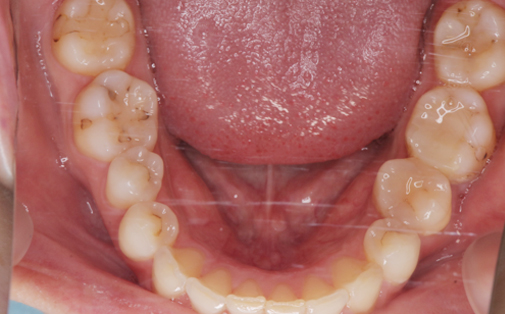

抜歯した親知らずを移植(3)

Before

After

左上の歯が折れています。折れた歯を抜き、親知らずの歯を移植しました。